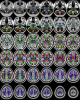

NTU-DSI-122 is a diffusion spectrum imaging (DSI) template constructed in the standard ICBM-152 space from 122 healthy adults. This template was built through incorporating the macroscopic anatomical information using high-resolution T1-weighted images and the microscopic structural information obtained from DSI datasets, rendering it to achieve a high anatomical matching to the ICBM-152 space. Therefore, this template can serve as a representative DSI dataset for a healthy adult population, and will be of potential value for brain research and clinical applications. This template is released in the original DWI format, so the users have the most freedom to perform their own advanced processing algorithms on NTU-DSI-122. NTU-DSI-122 is distributed under the terms of CC BY-NC-SA 4.0.